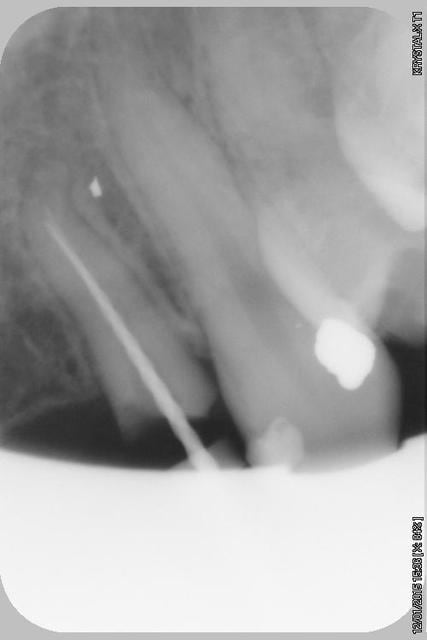

21/04/2015 à 11h34

Donc dans un premier temps,je décide d'essayer de retraiter 12/22, de toute façons ça ne peut pas être pire que ce qui tiens depuis 10 ans... enfin 12 mobilité quasiment 3.

ensuite Srew post (bouh...) et résine, afin de pouvoir poser un provisoire et réfléchir à l'avenir du parodonte...car il va y avoir un problème quelle que soit la solution choisie.

Sur la reprise de 22 je pense que tu as fais un beau "tout-droit" à l'apex... le canal devait suivre la courbure.

Tu es bon pour faire une chir-apicale dans quelques mois !

je pense que le tout droit existait déjà..

oup's j'ai omis la digue...

Chir apicale si on garde la dent...

Oui oui, c'est certain ! il y avait au moins une belle butée bien engagée. Ce qui expliquerai que l'ancien traitement n'allait pas jusqu'à l'apex.

Et avec les instruments de rotation continue agressifs de reprise d'endo que l'on a maintenant, on s'engage dans la butée et on la "termine"... ça m'arrive aussi de temps en temps... de toutes façons, repasser de vieilles butées comme ça, même les endos exclusifs n'y arrivent presque jamais et font une chir apicale d'emblée.